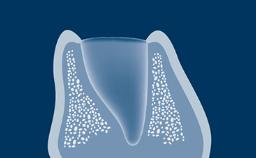

Após a extração dentária, um processo bem descrito de cicatrização ocorre no alvéolo. Uma série de eventos fisiológicos ocorre, resultando em cicatrização de feridas e regeneração óssea dentro do alvéolo. A reabsorção óssea resulta em alterações externas no rebordo alveolar.

O resultado dessa reabsorção é na maioria das vezes uma modificação significativa do contorno pré-extração da crista alveolar, que pode representar um problema para a reconstrução protética posterior. Por esse motivo, o conhecimento do processo de cicatrização após a extração dentária é essencial para o planejamento apropriado do tratamento com implantes sob orientação protética. Este módulo apresentará características anatômicas do osso alveolar e do alvéolo pós-extração e descreverá as alterações histológicas e dimensionais após a extração dentária.

- descrever as características anatômicas do processo alveolar, alvéolo dental e crista alveolar